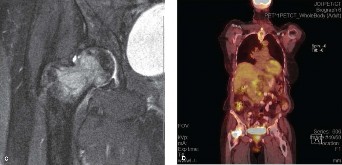

Figure 8–34 C–D

The correct answer is (A). The patient has metastases to the femoral neck and head. T1-weighted imaging shows a possible fracture line through the metastasis. Prophylactic stabilization of the femur with a cephalomedullary rod is not the best choice for this patient’s condition. With the significant neck and head disease, arthroplasty is indicated. Curettage and bone grafting is an inappropriate treatment for a metastatic lytic lesion; this is generally used for benign lesions. Radiation therapy is used in conjunction with surgical stabilization but will not treat the mechanical symptoms associated with the nondisplaced fracture that has already occurred and can lead to arthrofibrosis of the hip joint.